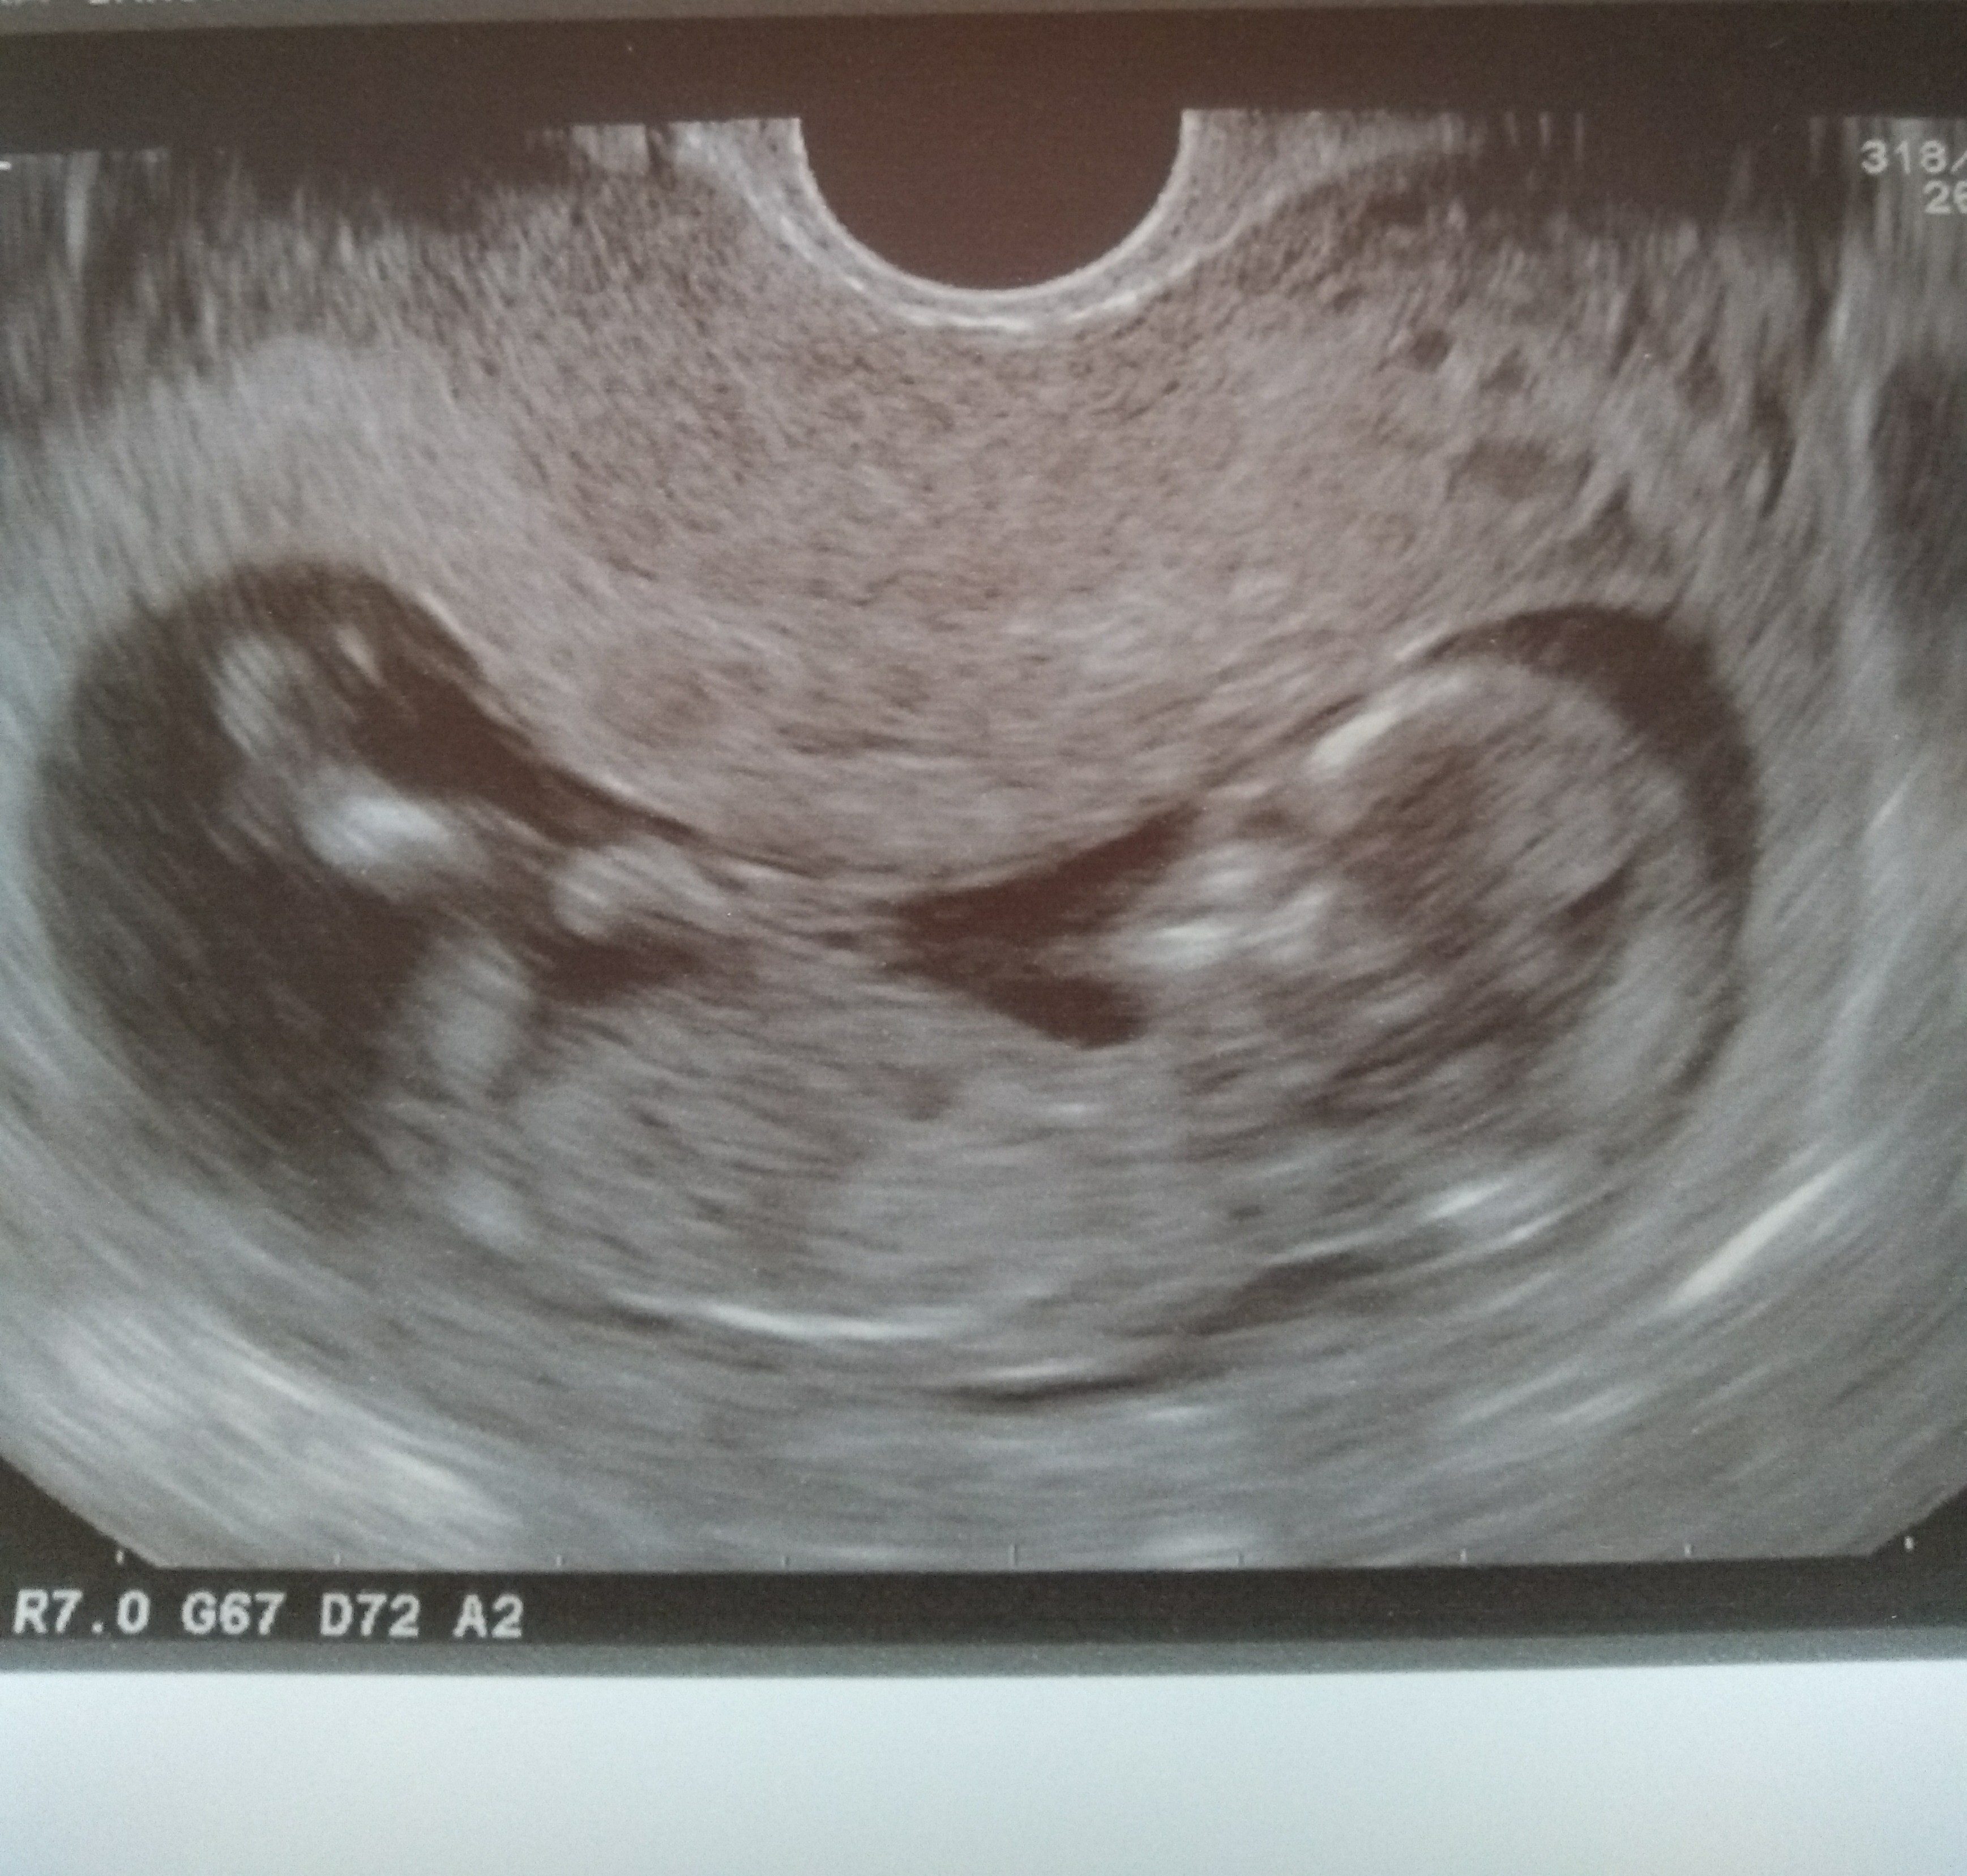

No ja już powszystko jest ok, maleństwo ma 6,5 cm. Przezierność karczku to 1,5. Wychodzi że to 12t6d

płeć niestety nie znana, bo się maleństwo bokiem odwróciło

Zobacz załącznik 920356

Super bobasekNo ja już powszystko jest ok, maleństwo ma 6,5 cm. Przezierność karczku to 1,5. Wychodzi że to 12t6d

płeć niestety nie znana, bo się maleństwo bokiem odwróciło [emoji14] Zobacz załącznik 920356